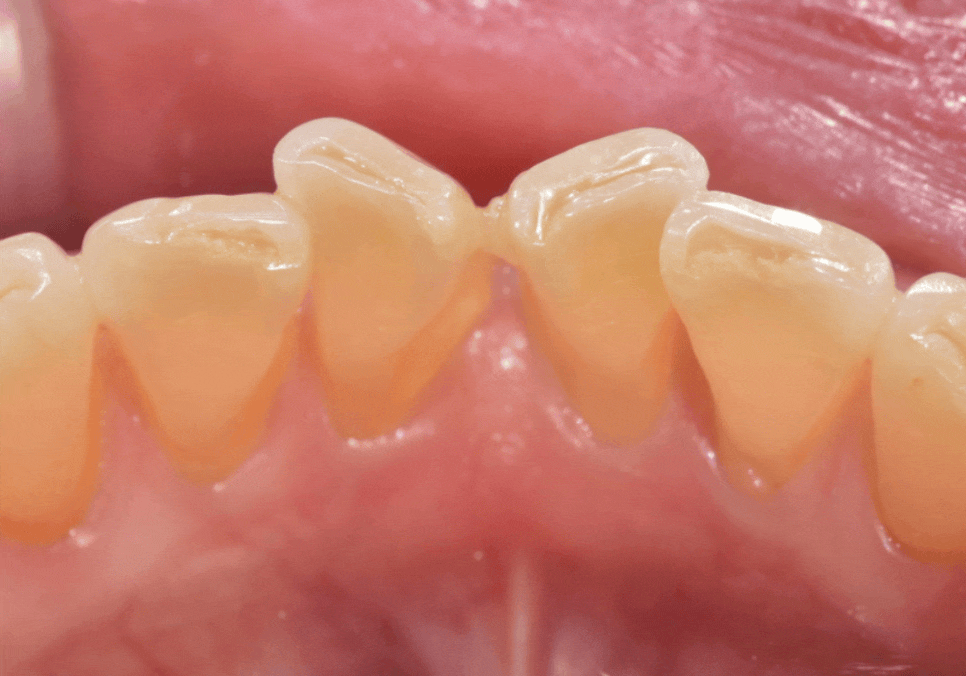

최근 아래 앞니가 나비 날개처럼 뻗어

고민이셨던 분이 찾아오셨습니다.

치아가 바깥으로 벌어져 있다 보니

평소 입술이 자꾸 걸리고

면 요리를 드실 때도 잘 끊기지 않아

무척 불편하셨다고 해요.